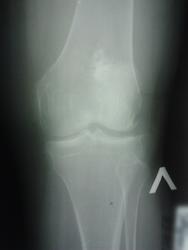

Больная 50 лет много лет страдает артритом правого коленного сустава, хромает. Имеется атрофия мускулатуры конечности, ограничение подвижности в коленном суставе. Несколько лет назад был перелом бедренной кости.

Рентгенограмма: кости сустава порозны; суставная щель значительно сужена; суставные края костей сустава узурированы; на границе средней и нижней трети бедренной кости следы сросшегося со смещением под углом перелома; в нижнем метафизе кости конгломерат известковых отложений; виден след продольной трещины кости, подходящий к метафизу.

В данном наблюдении обызвествление костного мозга, безусловно, можно связывать с кровоизлиянием, вызванным переломом. Но следует принять во внимание и некоторые биологические особенности - давнее костно-суставное заболевание, остеопороз, - возможно, способствующие обызвествлению гематомы в костном мозгу. Логичнее всего считать наблюдаемые обызвествления костного мозга как последствия некротических асептических процессов в костном мозгу, возникающих в результате рефлекторных расстройств кровообращения в сосудах последнего. Нужно также учитывать индивидуальные особенности организма, возможность расстройства трофики тканей.